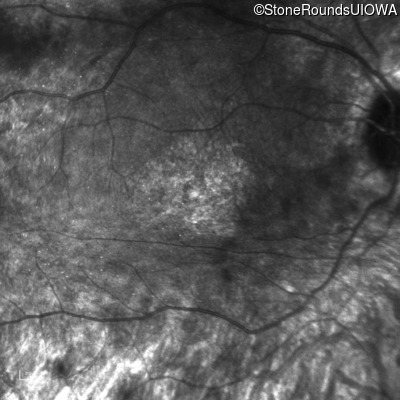

Infrared Fundus Photograph - Right - Hand Motion 1' sc

Exemplar

Infrared Fundus Photograph - Left - Hand Motion 6" sc